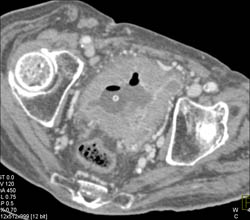

Diagnosis

Bladder Cancer